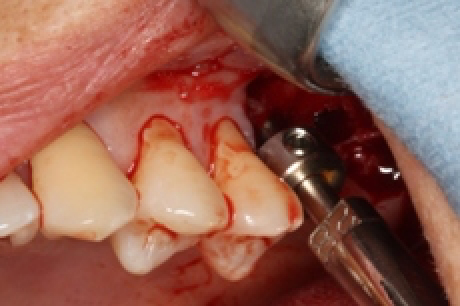

人工骨を挿入。内部の膜(上顎洞内の粘膜)を破らないように、慎重かつ大胆に進めていきます。2005年よりこの術式で行っておりますが、未だに一番緊張する瞬間でもあります。

紙切れの様な骨が、しっかりとボリュームがでました!っといっても、分かりにくいですよねぇ。